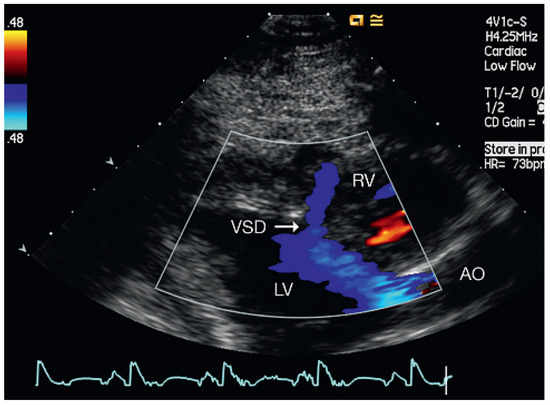

Muscular Ventricular Septal Defect After Mitral and Aortic Valve Replacement

by Augusto Aragão, Dorothea Vogel and Christoph Schmidt

Cardiovasc. Med. 2010, 13(5), 167; https://doi.org/10.4414/cvm.2010.01500 - 26 May 2010

We describe a case series of five patients who were referred to our cardiac rehabilitation department after mitral or aortic valve replacement, and whose transthoracic echocardiographic studies showed postoperative muscular septal defects. Full article

Show Figures

Figure 1